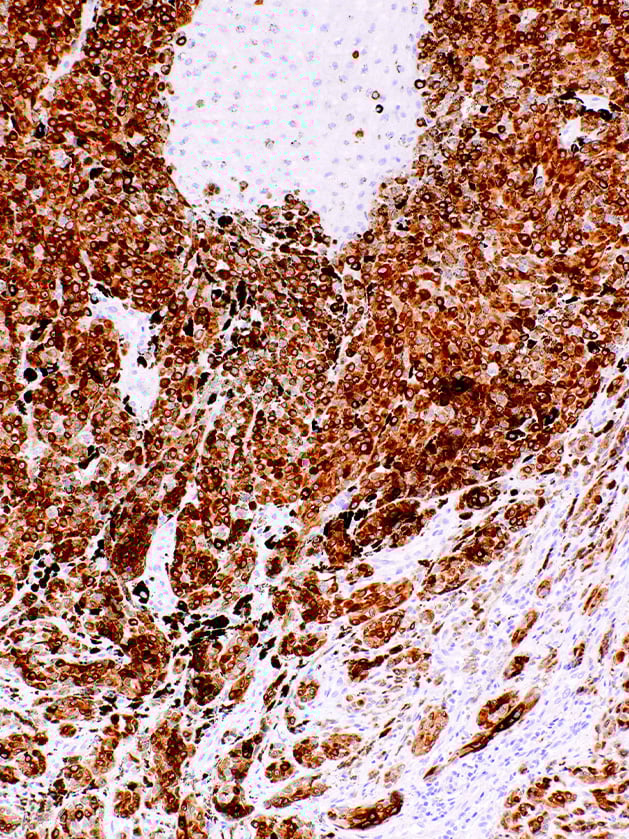

MART-1 (Melan A)

MART-1, also known as Melan A or Melanoma Antigen Recognized by T-Cells 1, is a protein antigen found specifically on melanocytes of normal skin, retina, and nevi, and not in other normal tissues. Anti-MART-1 is therefore useful as a marker for melanocytic tumours, and as an aid in establishing the diagnosis of metastatic melanomas.

POSITIVE CONTROL:

Melanoma, Skin